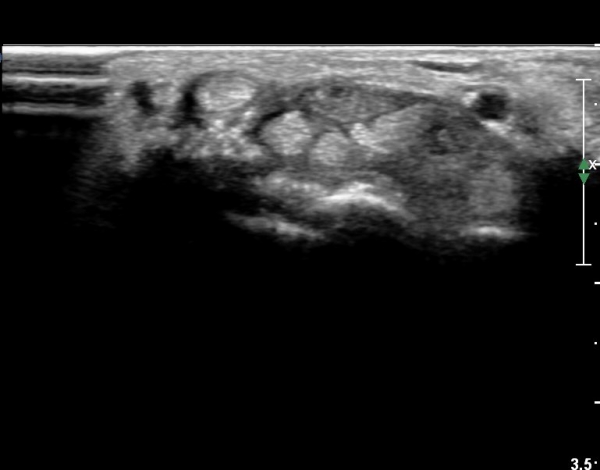

¼ö±Ù°ü ±ÙÀ§ºÎ Ⱦ´Ü¸é°Ë»ç¿¡¼ ±¼°î°Ç ½ÉºÎ¿¡ ¼®È¸È¼º À½¿µÀÌ Á¸ÀçÇϰí Àü¹ÝÀûÀÎ ¼öÁö ±¼°î°ÇÀÇ ºñÈÄ, Á¤Á߽ŰæÀÇ ºÎÁ¾°ú

ÈûÁÙ ¹× Á¤Á߽ŰæÀÇ Ç¥ÃþÀ¸·Î ÀüÀ§°¡ °üÂûµÈ´Ù, (»çÁø 3, 4,).